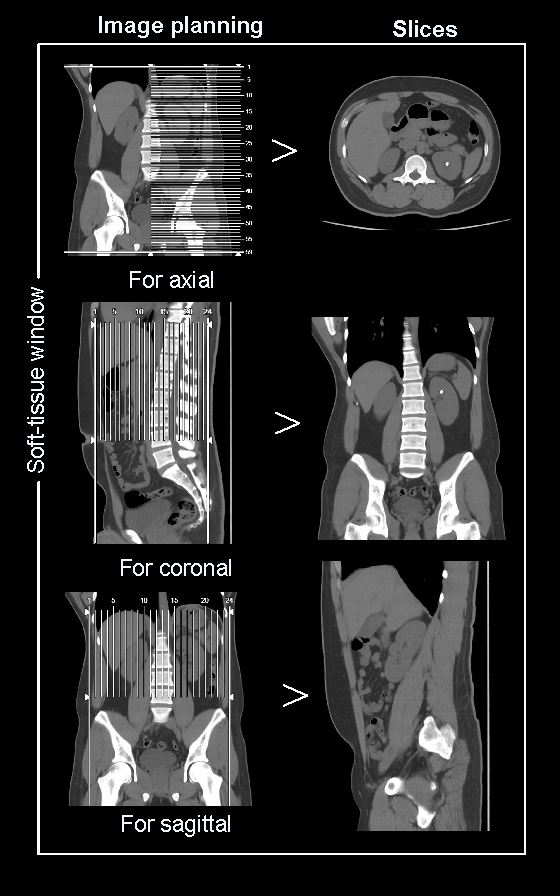

Scan planning

- If abdomen or upper abdomen, plan the scan slab from the dome of the diagram to the upper margin of the sacroiliac joints. However, lower end point of the scan can be extended to the pelvic region according to diagnostic needs.

- If abdomen and pelvis, plan the scan slab from the dome of the diagram to a level just below the ischial tuberosities.

- Conduct the scan under arrested inspiration.

- Axial, coronal and sagittal images in soft-tissue window (WL 500, WW 50) with ≤ 5mm slicethickness can be generated.

- Axial, coronal and sagittal images in bone-window (WL 3500, WW 350) with ≤ 3mm slice thickness can be generated.